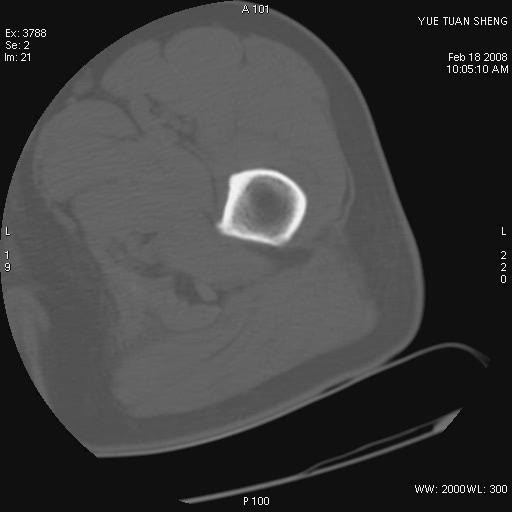

患者,男,56岁,左髋部疼痛1个月,x线:左股骨头高密度影,性质待定,右侧正常。左髋ct如图

左股骨颈区椭圆形磨玻璃样影,边缘明显硬化环环绕,其内见斑点状类钙化高密度影考虑 良性骨病-----骨纤,骨化性纤维瘤,内生软骨瘤。